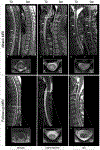

Aquaporin-4-IgG positive neuromyelitis optica spectrum disorder (AQP4+NMOSD) and myelin-oligodendrocyte glycoprotein antibody-associated disease (MOGAD) are antibody-associated diseases targeting astrocytes and oligodendrocytes, respectively. Their recognition as distinct entities has led to each having its own diagnostic criteria that require a combination of clinical, serologic, and MRI features. The therapeutic approach to acute attacks in AQP4+NMOSD and MOGAD is similar. There is now class 1 evidence to support attack-prevention medications for AQP4+NMOSD. MOGAD lacks proven treatments although clinical trials are now underway. In this review, we will outline similarities and differences between AQP4+NMOSD and MOGAD in terms of diagnosis and treatment.